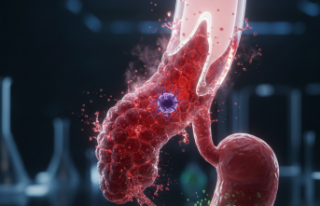

Bazen sağlıklı olduğunu düşündüğümüz şeyler, sessizce birikerek bizi yormaya başlar. Çoğumuzun bildiği kansızlık sorununun tam tersini düşünün; demirin vucudunda fazla olması durumu. Hemokromatozis (demir yüklenmesi) tam olarak böyle bir şey. Bahar aylarında yorgunluk sanılan o bitkinlik, aslında karaciğerinizin çığlığı olabilir mi? İnsan merak ediyor.

Vücut, besinlerden aldığı demiri atacak bir mekanizmaya sahip değil ne yazık ki. Biriken bu metal, kalpten pankreasa kadar her organı yavaş yavaş kuşatıyor. Belki de bu yüzden sabahları yataktan kalkmak bir yük gibi geliyor insana.